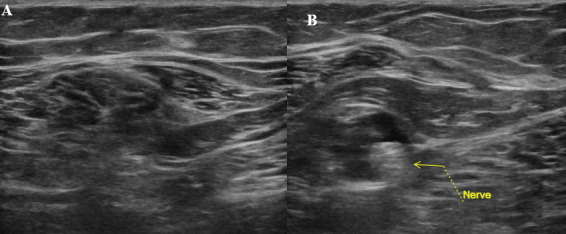

Case report: A 31-year-old female presented to our clinic with chronic neuropathic pain after sustaining a blunt injury to the medial aspect of the right leg 15 years previously while playing softball. Her pain was localized to the anteromedial lower leg and was not relieved by medical management and therapy. She temporarily had complete relief of her symptoms with ultrasound-guided hydrodissection. She was treated with surgical exploration and neurolysis, and postoperatively, the patient had no complications and complete relief of her pain.

Conclusion: We present a case of a 31-year-old patient who had perineural scarring and chronic neuropathic pain necessitating surgical exploration and neurolysis. Our case highlights the importance of investigating the etiology of neuropathic pain with several modalities and demonstrates the utility of ultrasound-guided peripheral nerve hydrodissection for both therapeutic and diagnostic purposes.